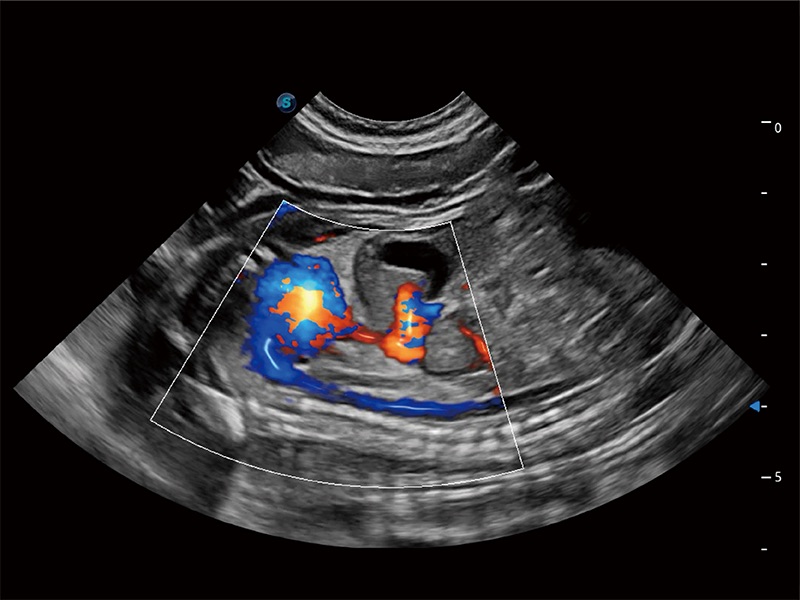

非线性融合造影成像充分利用谐波和基波信号,为难以观察的血流进行增强显像。可用于线阵、凸阵、微凸阵、相控阵探头。

ProPet 80 配备了丰富的心脏探头群、先进的成像技术和专业的心脏测量工具,可帮助动物医生为不同体型和生理结构的动物提供心脏和心肌功能的全面评估。